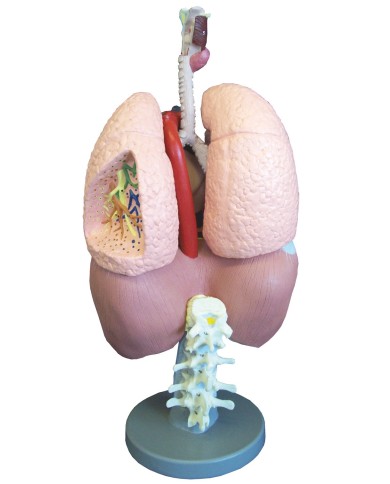

Kit composto da 3 modelli

Su base removibile

Modello di cuore di alta qualità scomponibile in 5 parti

La parete anteriore del cuore è staccabile per poter vedere i ventricoli.